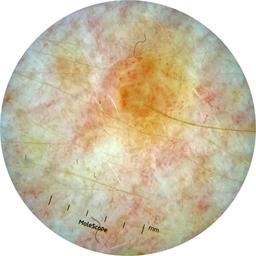

anatom_site_1 Head and neck

anatom_site_general head/neck

diagnosis_1 Malignant

diagnosis_2 Malignant adnexal epithelial proliferations - Follicular

diagnosis_3 Basal cell carcinoma

diagnosis_confirm_type single image expert consensus

image_type dermoscopic